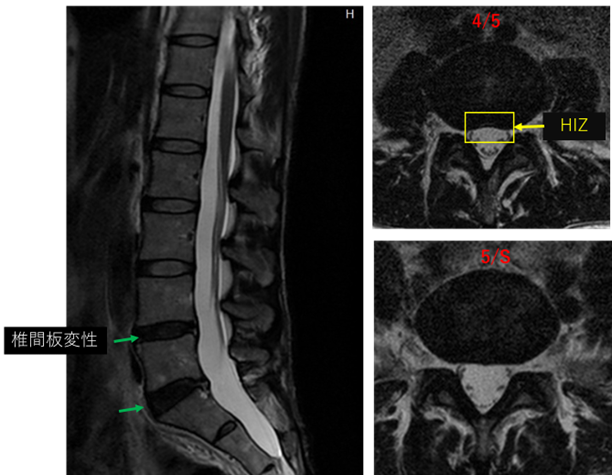

画像及び所見について

L1/2: 異常なし

L2/3: 異常なし

L3/4: 異常なし

L4/5: 椎間板変性、膨隆、線維輪断裂

L5/S: 椎間板変性、膨隆、線維輪断裂

以上の事が画像上認められます。

L4/5、5/S に

椎間板変性、線維輪断裂 を認め、主症状の原因の可能性が高い。